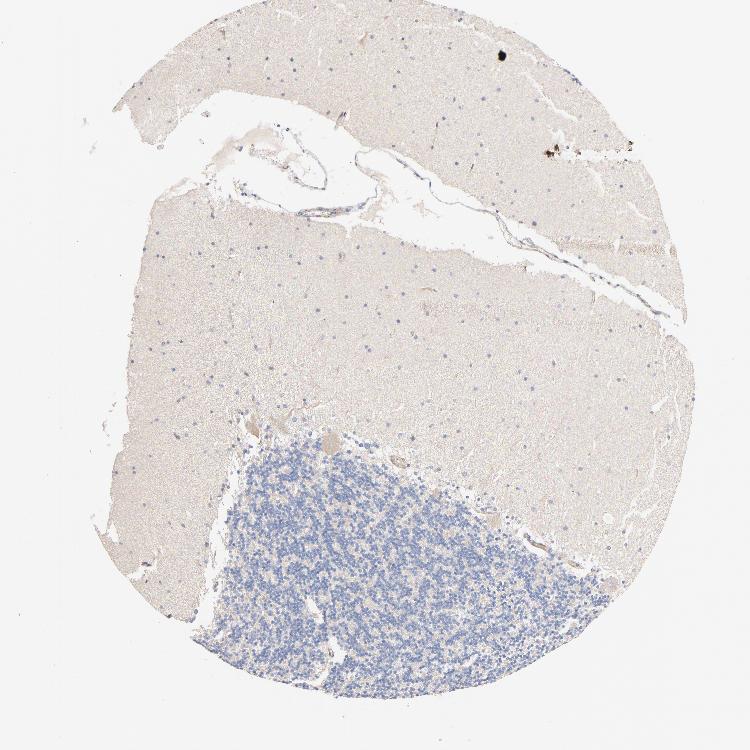

CEREBELLUM - Antibody stainingi

Antibody staining in the annotated cell types in the current human tissue is reported as not detected, low, medium, or high, based on conventional immunohistochemistry profiling in selected tissues. This score is based on the combination of the staining intensity and fraction of stained cells.

Each image is clickable and will lead to virtual microscopy that enables deeper exploration of all samples and also displays staining intensity scores, fraction scores and subcellular localization as well as patient and tissue information for each sample.

Antibody HPA003392Antibody HPA004636Antibody CAB069925

Purkinje cells LowMediumHigh

Cells in granular layer LowLowLow

Cells in molecular layer Not detectedLowNot detected